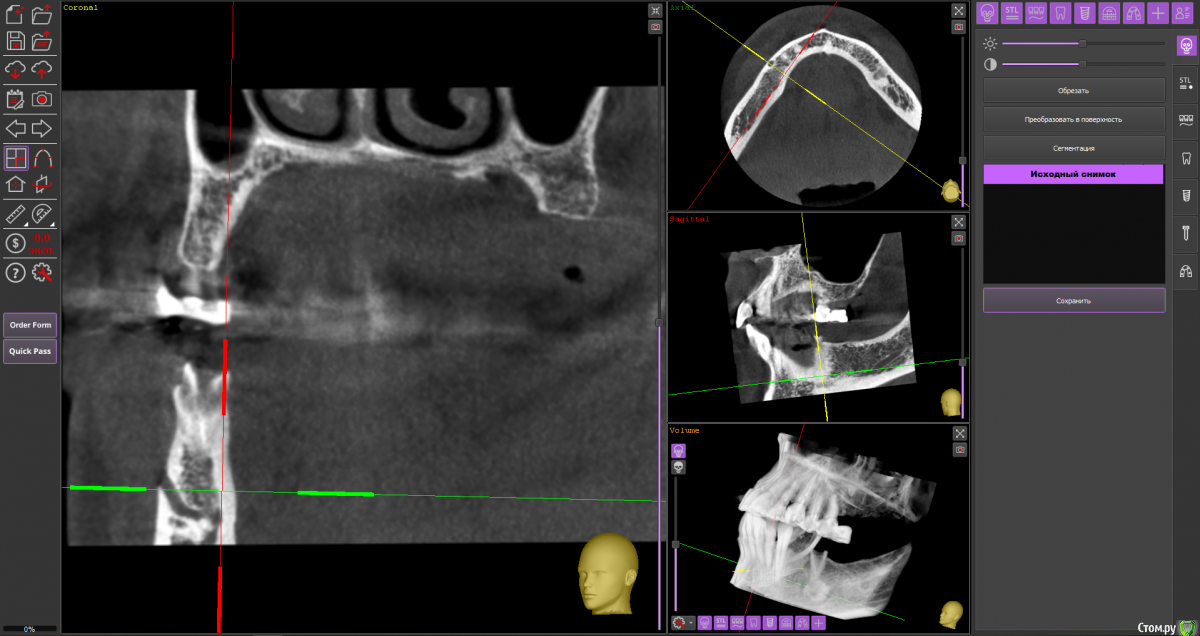

almaz7888 Опубликовано 11 февраля, 2021 Поделиться Опубликовано 11 февраля, 2021 (изменено) Доброе утро коллеги! Подниму тему. Данной пациентке планируется имплантация для замещения концевых дефектов на нижней челюсти. Зуб 3.5 думал удалить во время операции. Образование в области 3.5 это просто склероз кости? В области ментального отверстия справа также имеется какой-то очаг но меньших размеров. Изменено 11 февраля, 2021 пользователем almaz7888 Ссылка на комментарий